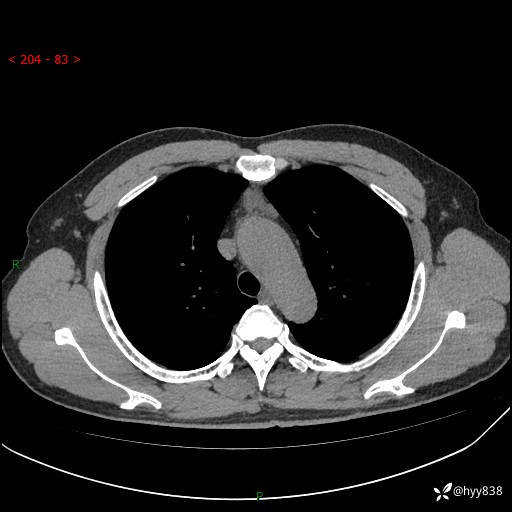

患者性别:女

患者年龄:49岁

简要病史:跟骨骨折,常规CT发现纵隔占位

胸部CT平扫